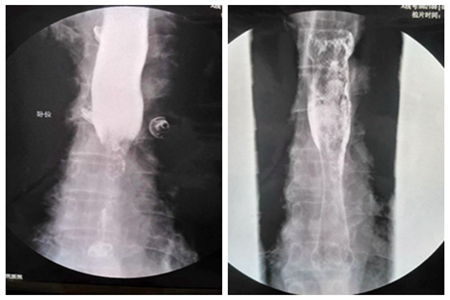

患者2,男,73岁,中下段食道癌放置支架前

(中下段食道癌支架置入术后6月,下端二次狭窄,行狭窄段再次支架置入术)、后对比图